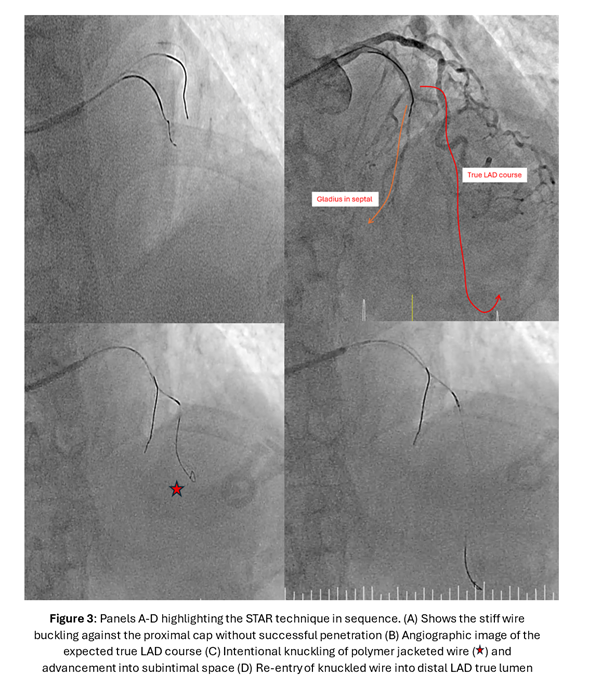

A torqueable microcatheter was used pre-emptively in view of expected difficulties wiring. The LAD occlusion was unsuccessfully crossed despite wire escalation from workhorse wires to polymer-jacketed and finally stiff wires with high tip loads. The wires either deflected into the septal branches or entered the subintimal space. Faced with the difficult situation of a patient with anterior STEMI with ongoing symptoms compounded by an acute-on-chronic mid LAD occlusion with no distal vessel visualization from collaterals to guide wiring, a decision was made to perform the Subintimal Tracking and Re-entry (STAR) technique. As a subintimal space had already been created from previous wiring attempts, a polymer jacketed wire with a pre-formed U-bend was advanced into the space forming a loop. Thereafter, the knuckled wire was pushed forward with the intention of bluntly dissecting the subintimal space and re-entering the distal true lumen. This successfully restored flow in the LAD and intravascular ultrasound images confirmed the wire to be in the mid LAD subintimal space. As the primary objective was to re-establish LAD flow and patient's symptoms improved, drug-coated balloon angioplasty of the subintimal space as an "investment" for subsequent definitive PCI was performed. A relook angiogram 3 months later showed patent mid LAD subintimal DCB segments with TIMI 3 flow. 2 drug eluting stents were placed in the left main to mid LAD for definitive PCI.

Case Summary